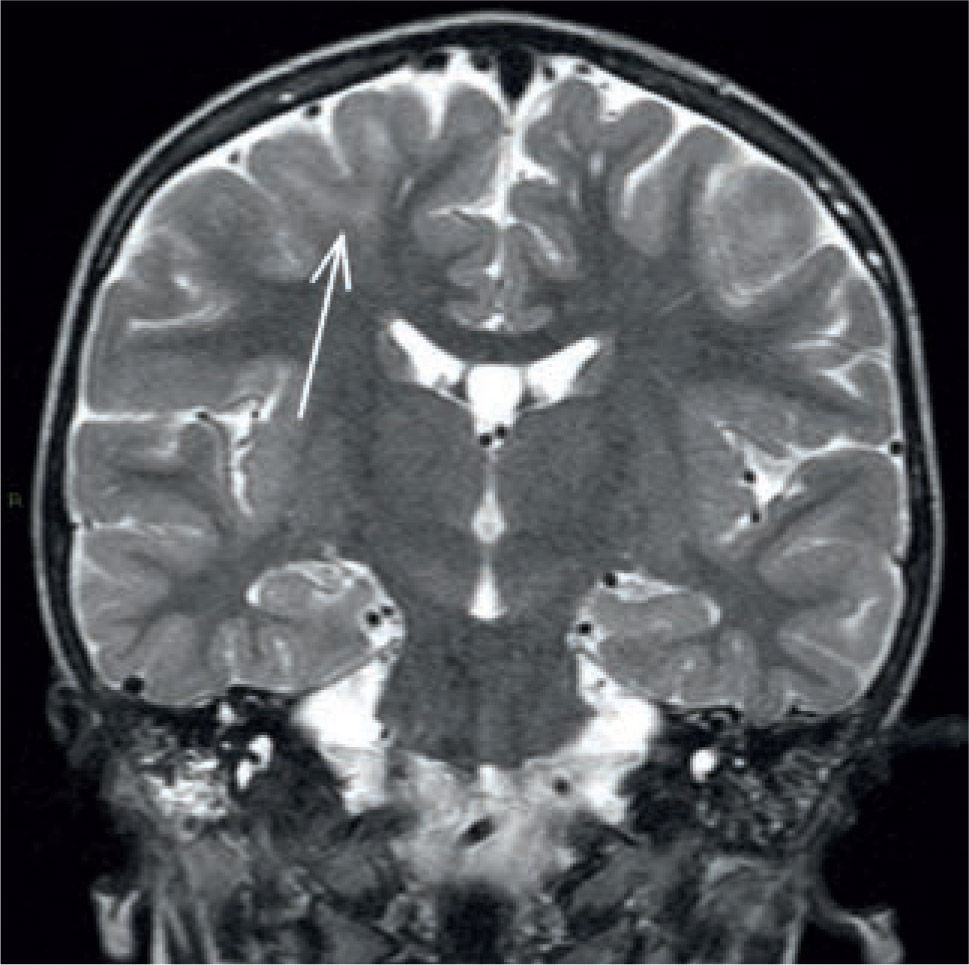

El hipocampo es una estructura arquitectónicamente compleja, generada por el enrollamiento de la corteza cerebral y la sustancia blanca sobre sí misma (Figura 3). La ETM tiene una apariencia característica con atrofia unilateral del hipocampo, debida principalmente a atrofia del segmento CA1, que produce un aumento de la señal en T2, producto de la gliosis con pérdida neuronal y a la pérdida de la arquitectura interna, con la consiguiente menor diferenciación de la sustancia gris y sustancia blanca; la RM tiene una sensibilidad entre 75 y 90% para su detección. Los mejores resultados se obtienen en casos de ETM unilateral, con RM y estudio EEG concordantes. Los pacientes con ETM tienen un muy buen pronóstico postquirúrgico con hasta 80% de pacientes libre de crisis a l año y un 66% a largo plazo, lo que tiene un impacto muy significativo en la calidad de vida de estos pacientes (21).

3Imágenes volumétricasLa ETM se caracteriza por una disminución del volumen hipocampal, que generalmente es evidente en las imágenes convencionales. Sin embargo, las dificultades se producen en los casos leves, donde sólo existe una discreta disminución de volumen o en lesiones bilaterales simétricas, difíciles de detectar para el ojo humano (Figuras 15 y 16).